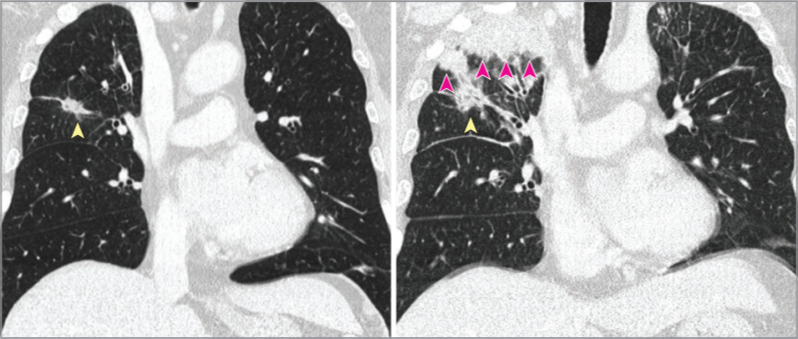

那么我带你看一个病例图片:

该患者为ROS1阳性的肺癌患者,在初期予色瑞替尼靶向治疗后肿瘤缩小;

但是改用克唑替尼(因医保报销原因)后三周,出现干咳,并且右上肺叶出现新发实变灶(右图 vs 左图);

影像科医生考虑肺癌进展,癌性淋巴管炎。

然而,这个病例后来医生做了CT引导下穿刺活检,诊断并不是肺癌进展,而是结节病样反应。[1]

分享这个病例想告诉大家,肺癌进展判断需要综合考虑多方面因素,类似的影像学改变除了肿瘤进展,你还需要鉴别真菌感染(因肿瘤患者免疫低下)、间质性肺病(治疗相关)、良性病变比如结节病样反应(治疗相关)等。